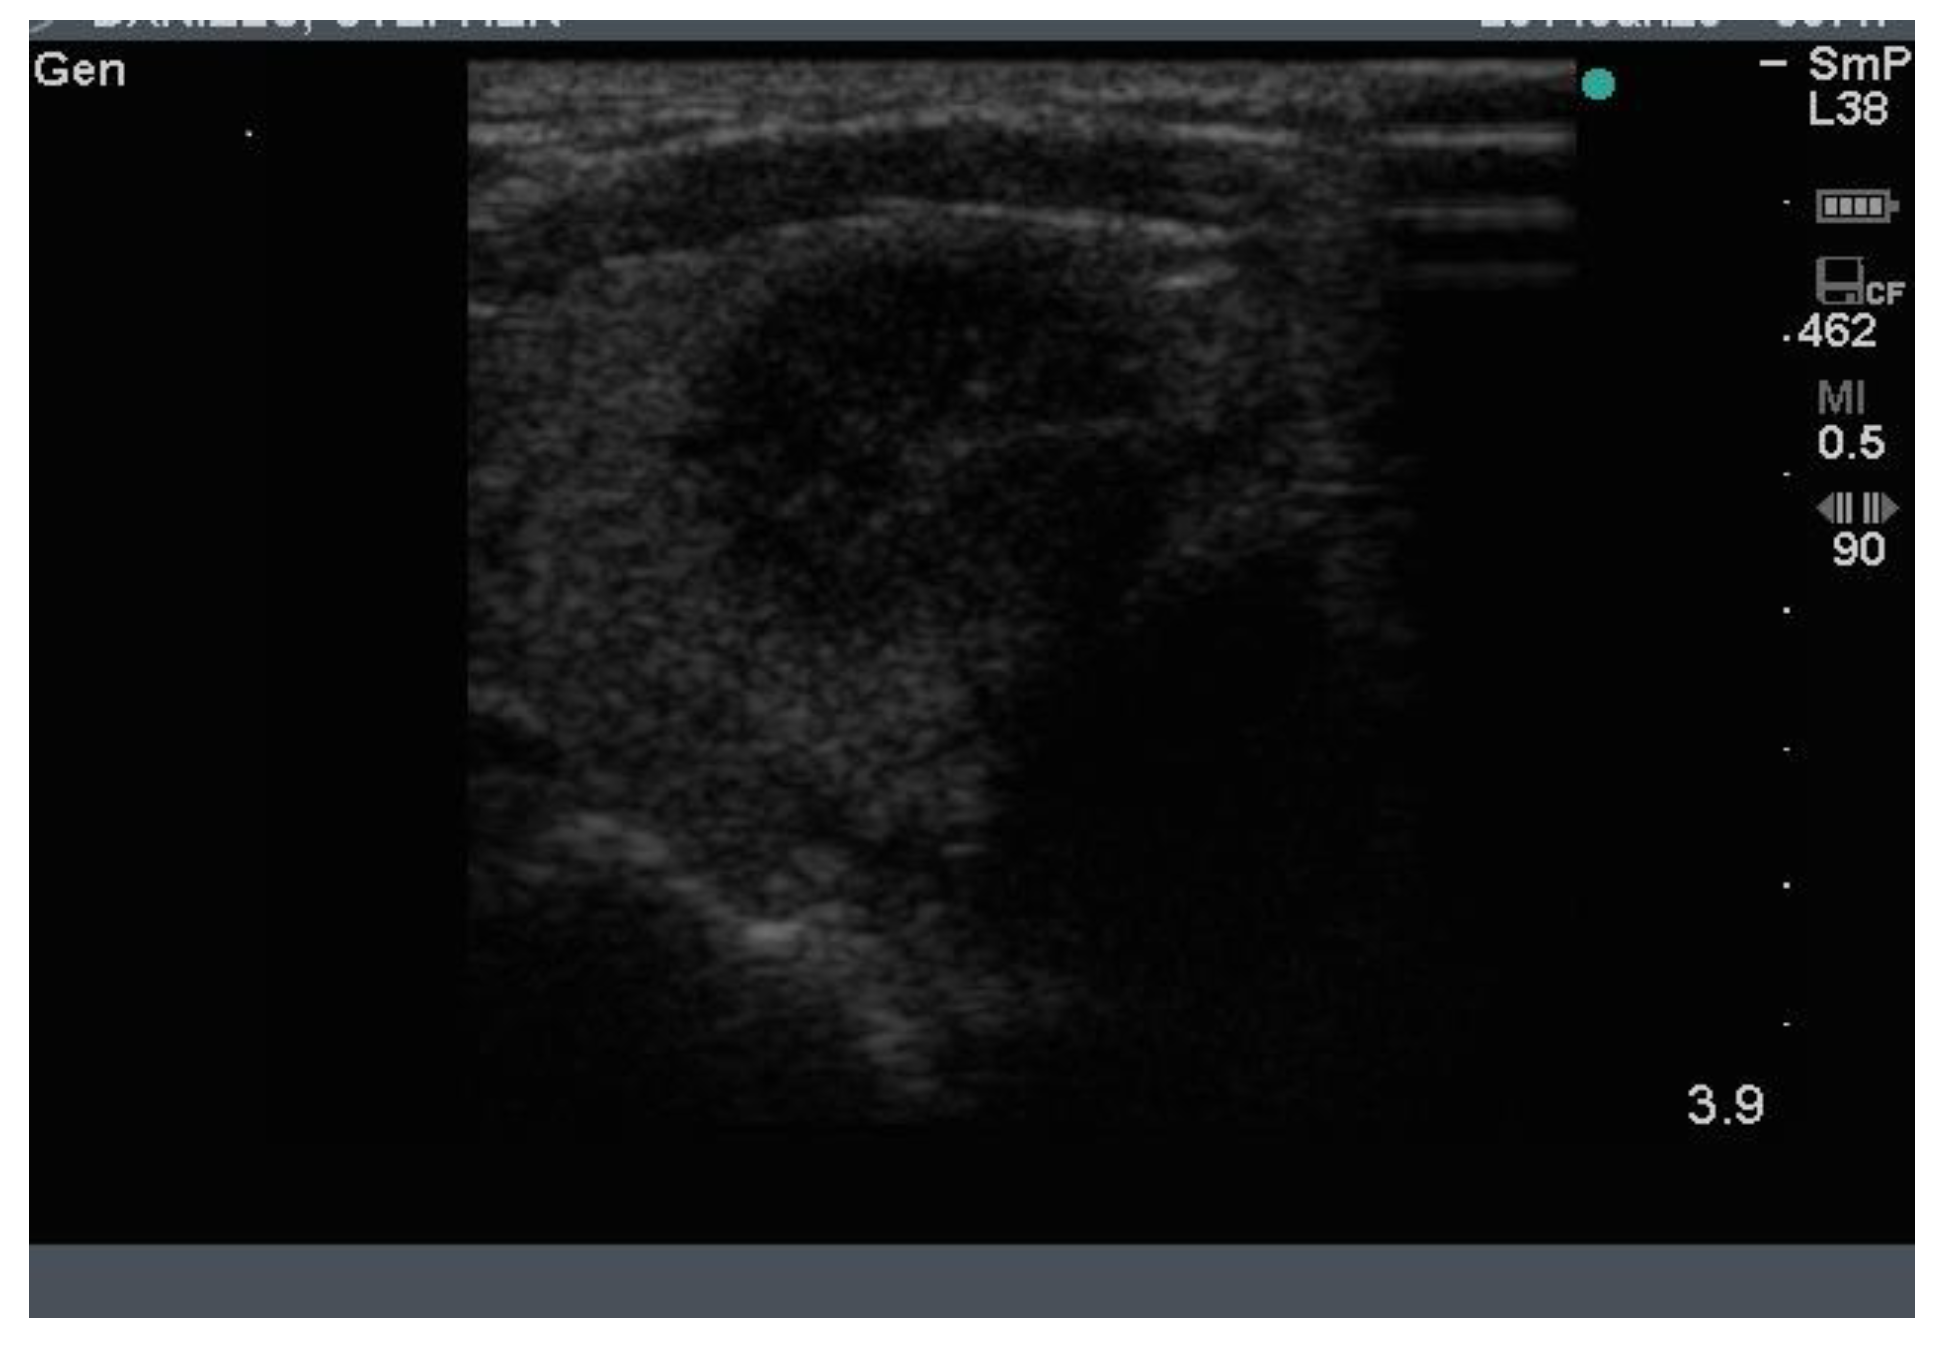

8. Calcification

The normal gland does not contain any calcification. The presence of calcification in association with nodules generally indicates that the nodules are long standing and therefore likely to be benign. However, breaks in the wall of a calcified nodule suggest that the nodule is a cancer which has invaded into the surrounding thyroid tissue and is considered a suspicious feature of a nodule [7]. Calcification is sometimes seen as spots or sheets scattered throughout the thyroid. Calcification surrounding a thyroid nodule, giving it the appearance of a “bone ball”, can be felt as a hard, mobile lump on neck palpation that is crunchy on biopsy. Chronic linear or egg shell calcification is associated with shadowing because the ultrasound waves are unable to pass through calcified tissue (Figure 8A,B). Calcification is also seen in the thyroid of patients with chronic Hashimoto thyroiditis and Graves’ disease.

Figure 8. In (A) linear calcification in the anterior aspect of a benign 15 mm nodule is seen as a curved bright hypoechoic shelf (arrow) that blocks the transmission of the ultrasound waves, so the nodule behind appears to be very hypoechoic, as in a cyst. In (B) is seen a small hypoechoic calcified nodule (upper arrow) and below it, a larger nodule with linear calcification in its anterior surface (lower arrow).